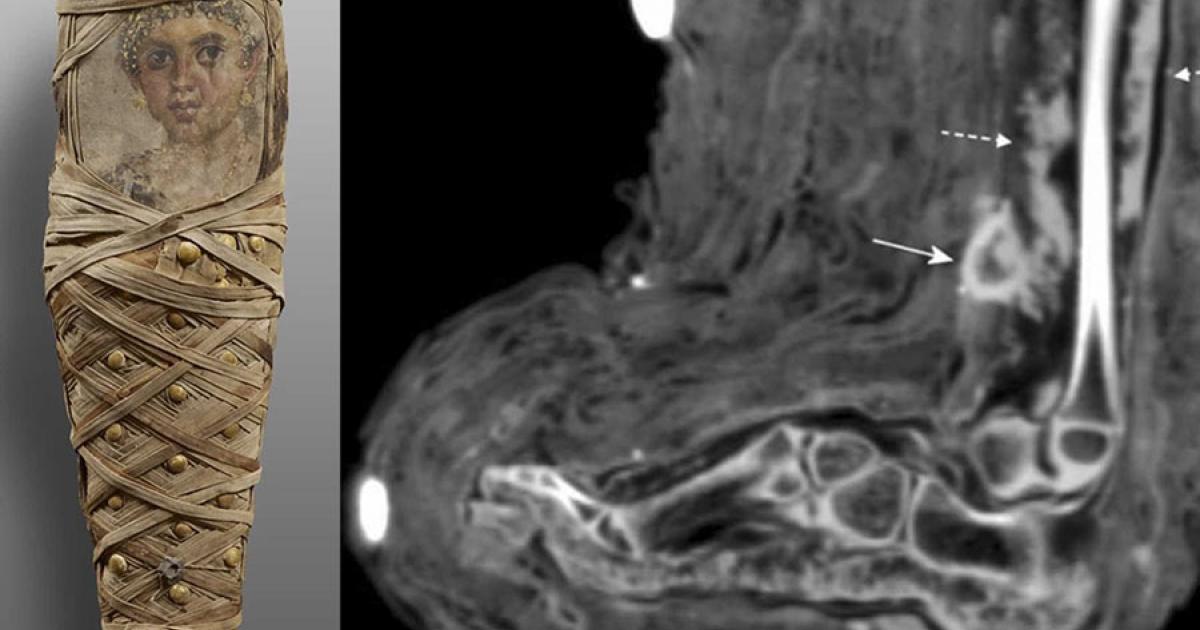

Photograph of ancient Egyptian child mummy from the Tomb of Aline, discovered in Hawara. (Panzer et. al / International Journal of Paleopathology)

The girl’s mummy was one of eight recovered from the Tomb of Aline, which was unsealed in 1892 by German archaeologist Richard von Kaufmann in the Faiyum Oasis southwest of Cairo. The tomb was named after one of its occupants, a woman who was referenced in the tomb’s inscription. Her mummy was buried alongside those of two female children who were believed to be her daughters. The little girl with the wound was one of these.

Top image: On the left, photograph of ancient Egyptian child mummy from Tomb of Aline, discovered in Hawara. On the right, CT scan of soft tissue infection in the lower leg, showing a mass consistent with dried pus. Source: Panzer et. al / International Journal of Paleopathology